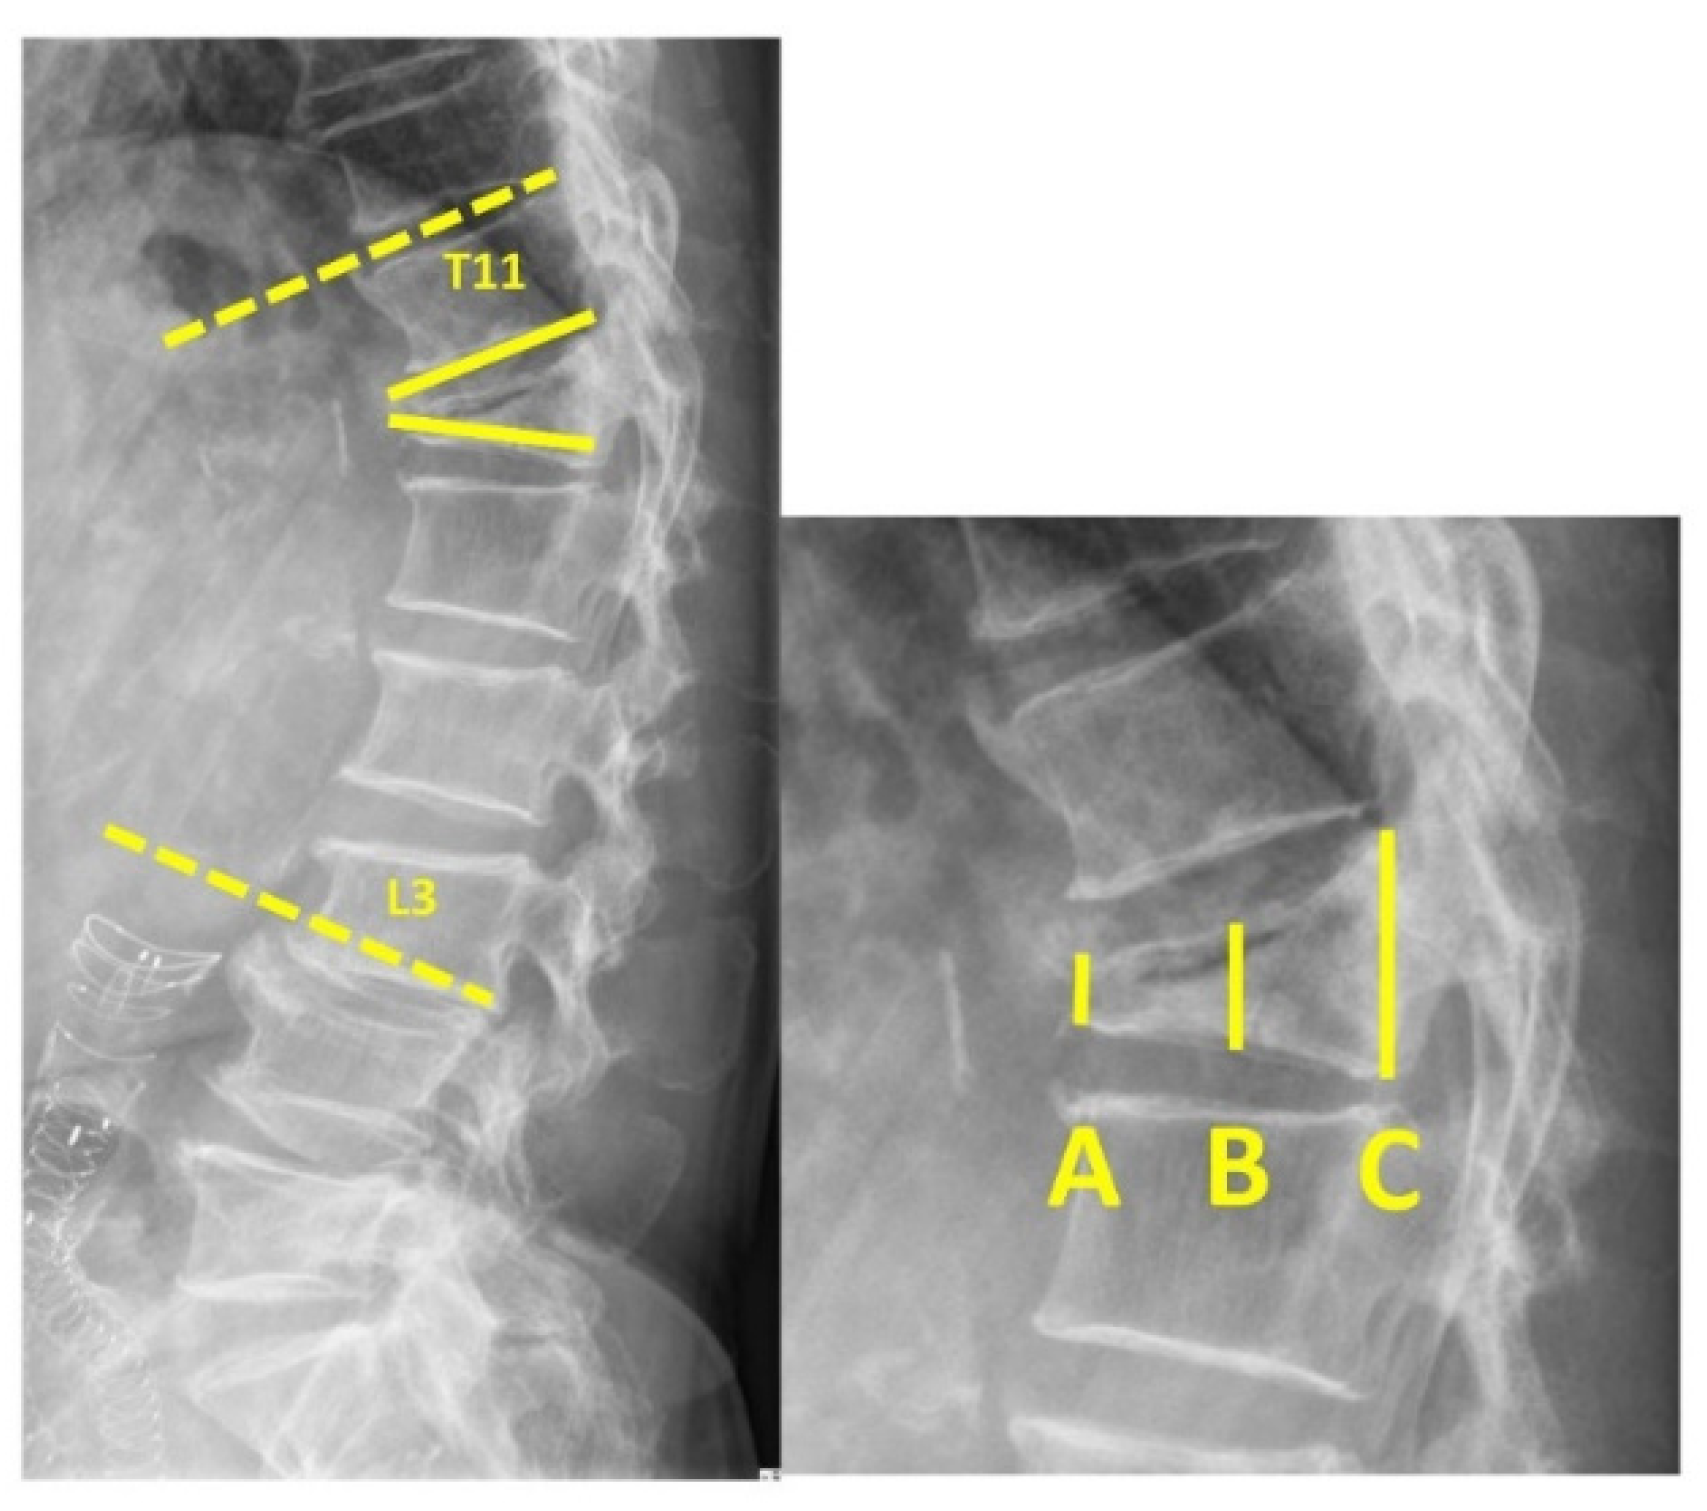

Diagnostics Free FullText “Double Cross Sign” Could Be an Indicator of an Adequate Amount

Diagnostics Free FullText “Double Cross Sign” Could Be an Indicator of an Adequate Amount Spinejack Indications Pain doesn't have to be permanent. Spinejack ® procedure taking restoration to new heights. You can get up to 12 months of relief with spinejack. Spinejack system instructions for use. The spinejack ® system is indicated for use in the reduction of mobile spinal fractures that may result from osteoporosis, trauma (fractures. The spinejack system offers three implant kit sizes:. Spinejack Indications.

Diagnostics Free FullText “Double Cross Sign” Could Be an Indicator of an Adequate Amount Spinejack Indications A prospective, international, randomized, non. You can get up to 12 months of relief with spinejack. It is intended to be used. Indications for use the spinejack system is indicated for use in the reduction of mobile spinal fractures that may result from osteoporosis,. Spinejack ® procedure taking restoration to new heights. Summary of spinejack characteristics and indications for patients’. Spinejack Indications.